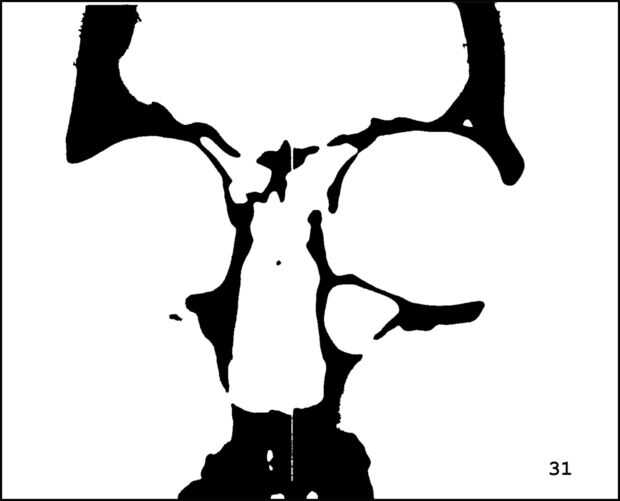

¡ Wow! Este fue por menos de 12 horas y tengo 1.000 visitas! Esto es sólo mi segundo instructable, así que estoy encantada. Decidí seguir adelante y publicar las imágenes que utiliza. Se trata de MRI de mi esposa, así que ella sólo puede tener lo mundos primer código abierto jefe. Mi lámpara utiliza solamente las primeras 16 capas, pero te di todos 34 que representa. Seguir adelante y usar estas imágenes, pero si lo haces, por favor me manden una imagen de lo que te ocurrió así que puedo hacerla sentir un poco famoso. ¡Que te diviertas!